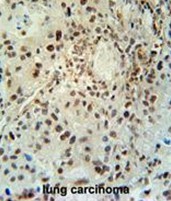

Supportive validation

- Submitted by

- Acris Antibodies GmbH (provider)

- Main image

- Experimental details

- ABHEB Antibody (C-term) (Cat. #AP50029PU-N) immunohistochemistry analysis in formalin fixed and paraffin embedded human lung carcinoma followed by peroxidase conjugation of the secondary antibody and DAB staining. This data demonstrates the use of the ABHEB Antibody (C-term) for immunohistochemistry. Clinical relevance has not been evaluated.